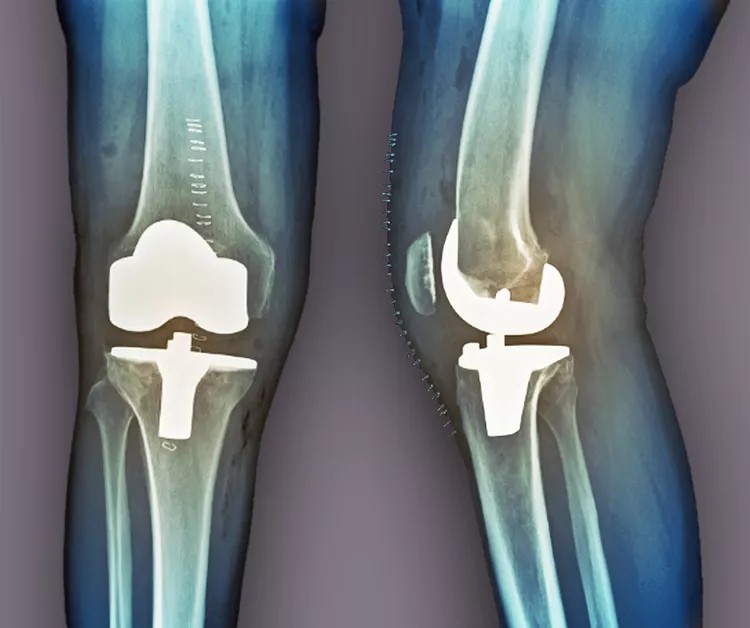

當其他療法失敗時,關節置換術是最后選擇。在這種手術中,醫生會切除膝蓋受損部位,并用金屬或塑料部件代替。如果這種方法不起作用,通過融合連接骨頭可能會緩解疼痛。缺點是,在這種手術后,其他關節最終會承受更大的壓力,以補償融合關節的運動損失。